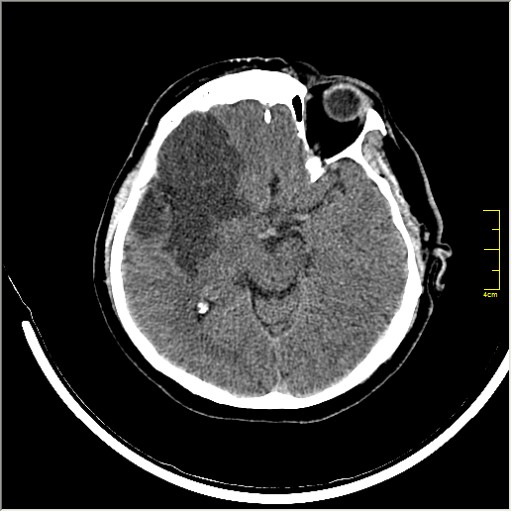

Этот признак называется [Dense MCA sign]; за счёт наличия тромбоза в её просвете. Этот признак является одним из ранних указующих КТ признаков при ишемическом инфаркте головного мозга. Более подробно об этом вы можете прочитать здесь: http://www.radiologyassistant.nl/en/483910a4b6f14.

Ну и для полноты картины, привожу контрольные КТ сканы выполненные через 24 часа: